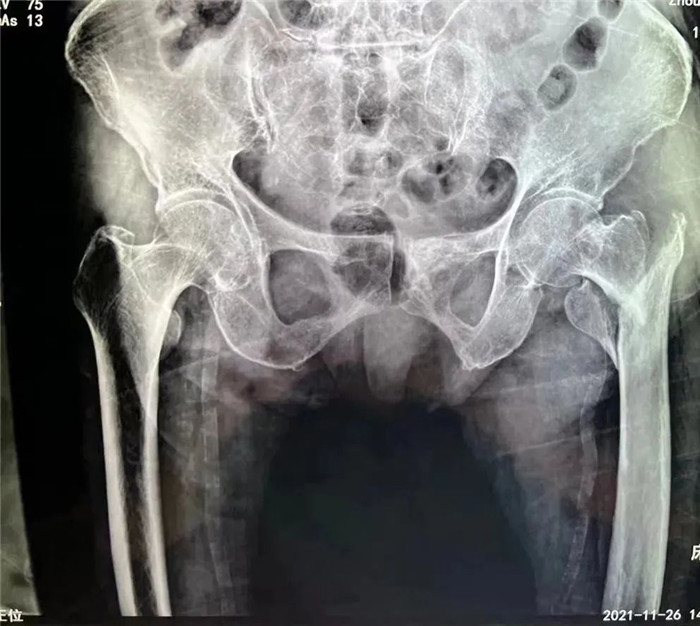

洪阿婆家住東港,前段時間在家行走時不慎摔倒,疼痛難忍,無法活動。家人遂即送至我院,診斷為股骨粗隆粉碎性骨折。這是一種老年人常見的損傷,多是在摔倒時暴力導(dǎo)致股骨近端骨質(zhì)連續(xù)性斷裂,造成骨折。但是因老人年事已高,同時伴有腦梗死、肺部感染等多種并發(fā)癥,無論采取保守治療還是手術(shù)治療,都存在一定風險,聽到這話的家屬異常沉重。

羅主任表示,老年人最怕摔跤,髖部骨折是造成老年人死亡率第一的疾病,因此被稱為“人生的最后一次骨折”。許多人認為老年人做手術(shù)的風險太大了,以為臥床休息、保守治療是最安全的,擔心手術(shù)會要了老人的命。其實對于老年人采取保守治療的死亡率遠遠高于手術(shù)治療。因為,老年人股骨頸骨折后長期臥床對老年人的身體和心理打擊都很大,一旦長期臥床將迅速出現(xiàn)心肺功能的代謝障礙、壓瘡、肺炎、泌尿系統(tǒng)感染、血栓等一系列繼發(fā)性疾病,其中任何一種疾病對老人來說都是致命的。